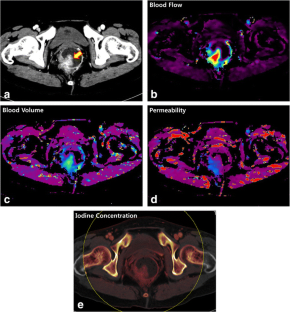

Fig. 2